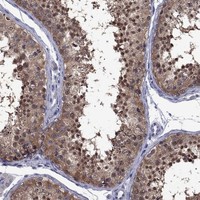

Immunohistochemical staining of human testis shows strong nuclear and cytoplasmic positivity in cells in seminiferous ducts.